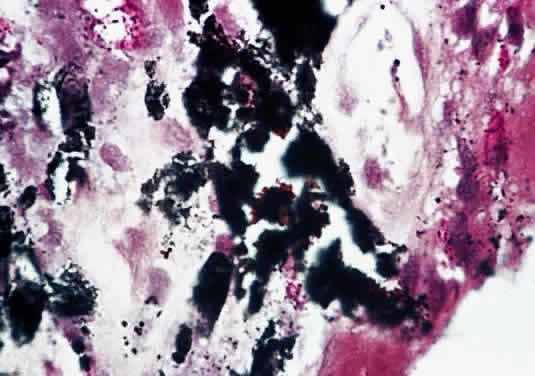

Tubercles are the characteristic lesions of primary tuberculosis. They begin as an acute inflammation marked by accumulation of polymorphonuclear leukocytes. After the development of hypersensitivity, the leukocytes are replaced by lymphocytes and macrophages as a granulomatous reaction develops. Central caseation is surrounded by a ring of epithelioid cells, which may fuse to form multinucleated giant cells (Fig. 1). Peripherally are found lymphocytes, macrophages, and proliferating fibroblasts.

Fig. 1. Tuberculous iris mass with caseating granuloma (hematoxylin and eosin, × 110). (Dunn JP, Helm CJ, Davidson PT: Tuberculosis. In Pepose JS, Holland GN, Wilhelmus KR [eds]: Ocular Infection and Immunity, p 1413. St Louis, Mosby-Year Book, 1996.)